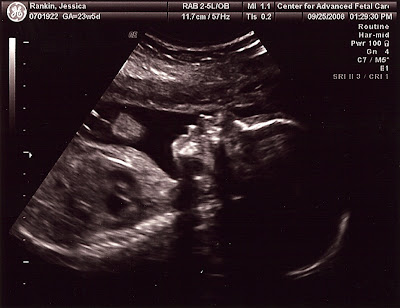

Well, we hit the 23 week mark with Baby Rankin. We went in this morning for our sonogram that showed us that we have a healthy baby growing exactly to the date! It was very exciting for all of us to see, we especially felt blessed when we watched the baby yawn. Technology is so amazing! All the vitals and development looked wonderful. Praise be to God! Ainsley is excited and anxiously awaiting when the baby will arrive.

We also would like to ask for your prayers though at this time. During the sonogram, they discovered that I have placenta previa. I've switched to a high-risk doctor and have had an appointment with him. He is a wonderful doctor and very reassuring. We'll be monitoring the situation every 4-6 weeks to see if the placenta migrates away from what Matthew refers to as "the exit hatch." If not, I'm looking at a C-section for this baby. We ask that everyone would pray that both mom and baby stay healthy, that we would be able to deliver naturally, and that the doctors would have wisdom in our management plan. Thank you in advance for your prayers, we'll keep you posted.